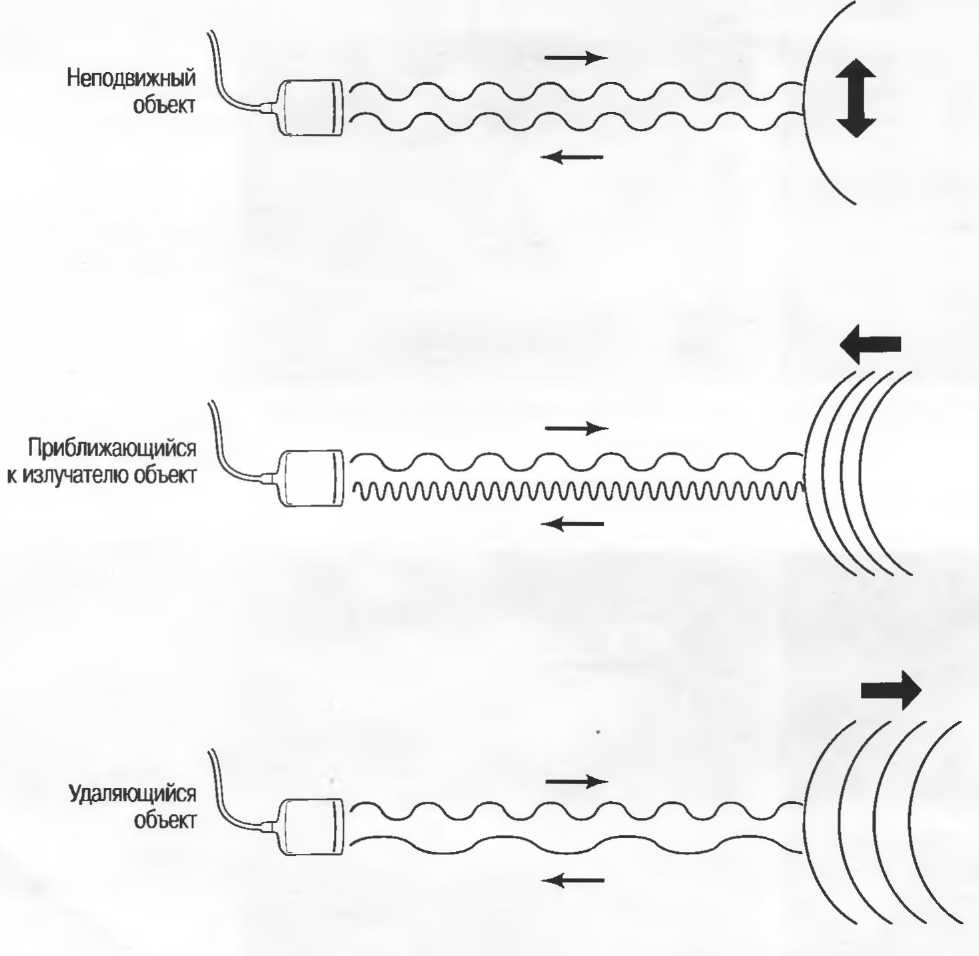

Эффект Доплера

При отражении от неподвижного объекта ультразвуковые волны будут иметь такую же частоту, как и испускаемые датчиком. Если отражающий объект движется по направлению к излучателю, частота отраженного сигнала будет выше, чем излучаемая частота. И наоборот, если отражающий объект движется от датчика, отраженная частота будет ниже, чем излучаемая частота.

Разница между излучаемой и принимаемой частотами пропорциональны скорости, с которой объект приближается к излучателю или удаляется от него. Это явление называется эффектом Доплера, а разница между излучаемой и принимаемой частотами называется доплеровским сдвигом частот.

Движение по направлению к датчику увеличивает отраженную частоту.